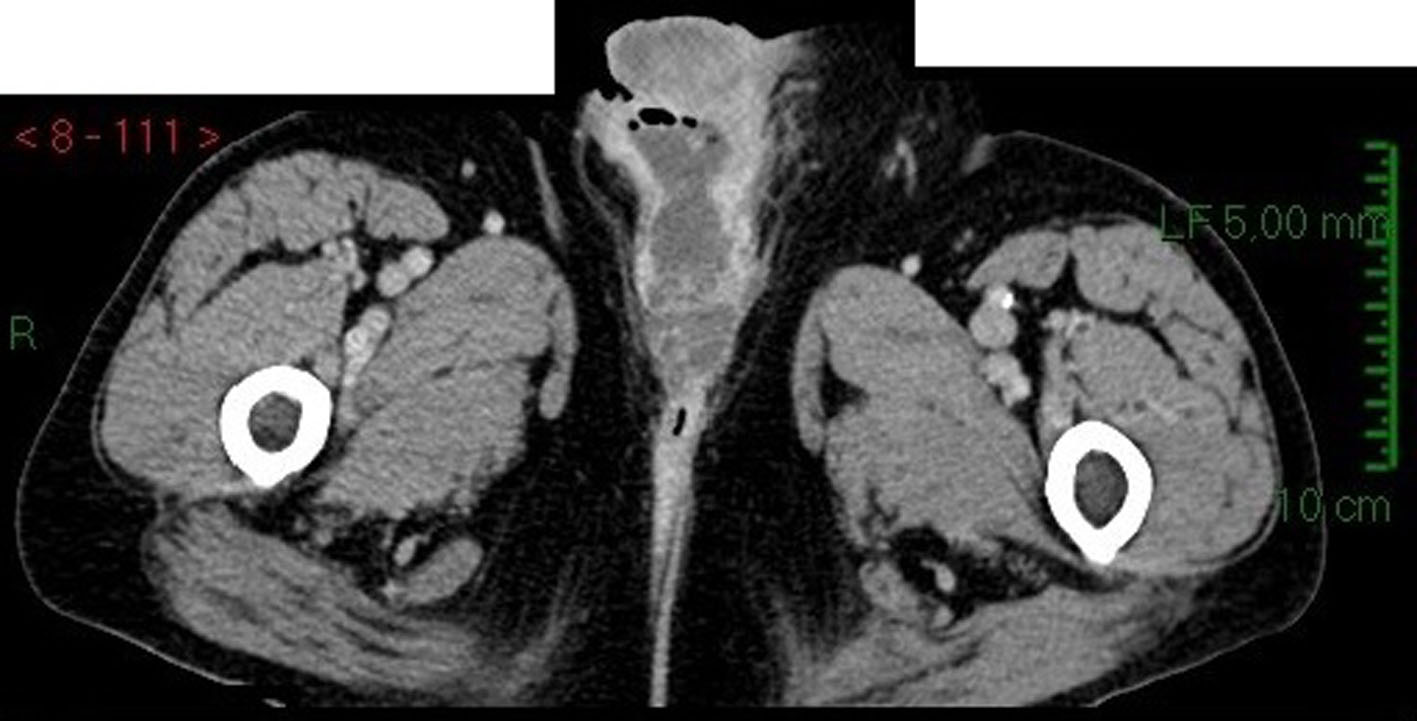

We admitted an 81-year-old man to our hospital for fever and a scrotal ulcerative lesion with clear signs of infection. His past medical history included bilateral cryptorchidism surgically treated in young age, inguinal hernia and hypertension. Scrotal examination showed an indolent malodorous scrotal ulcer, discharging abundant purulent and mucinous fluid. We performed a bacterial swab and cold biopsy and started empirical antibiotic therapy. After a few days, fever disappeared and white blood cells dropped within normal range. Bacterial swab was positive for Citrobacter farmeri and Staphylococcus saprophyticus, therefore, we started a targeted antibiotic therapy. Biopsy showed atypical cells, macrophages, bacteria and mucin. Abdomen/pelvis CT scan (Fig. 1) revealed a massive left inguinal hernia containing fat and bowel and a small contralateral inguinal hernia containing only adipose tissue. CT showed a large perineal and scrotal area with multicystic aspects and air microbubbles, as a result of an abscess (Fig. 2, 3); no intraperitoneal or retroperitoneal fluid was observed.

![]() Click for large image | Figure 3. CT scan image: transversal section of scrotal area in venous phase showing contrast enhancement of tumor tissue. |